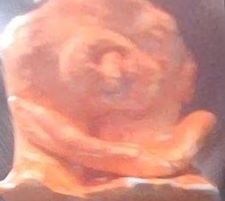

Comment on Kenneth4981's Artwork

View Kenneth4981's portfolio

Which artwork you would like to comment on?